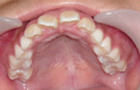

飛び出して持ち上がってしまっていた前歯が降りてきました。

横向き寝やうつぶせ、頬杖などに気をつけて治療をし、V字型だった歯並びが本来のU字型になってきました。

これで永久歯を抜かないで治療することができるようになりました。飛び出していた前歯がだんだん咬みあってきました。